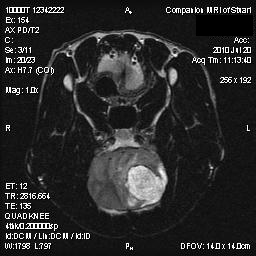

Companion MRI is the only full-time small-animal veterinary magnetic resonance imaging center in central Connecticut serving clients from all over New England, New York, and New Jersey. MRI for dogs and cats has the same clinical indications and diagnostic benefits as MRI scans for humans. We are excited to offer this affordable, superior diagnostic tool to all veterinarians and clients.